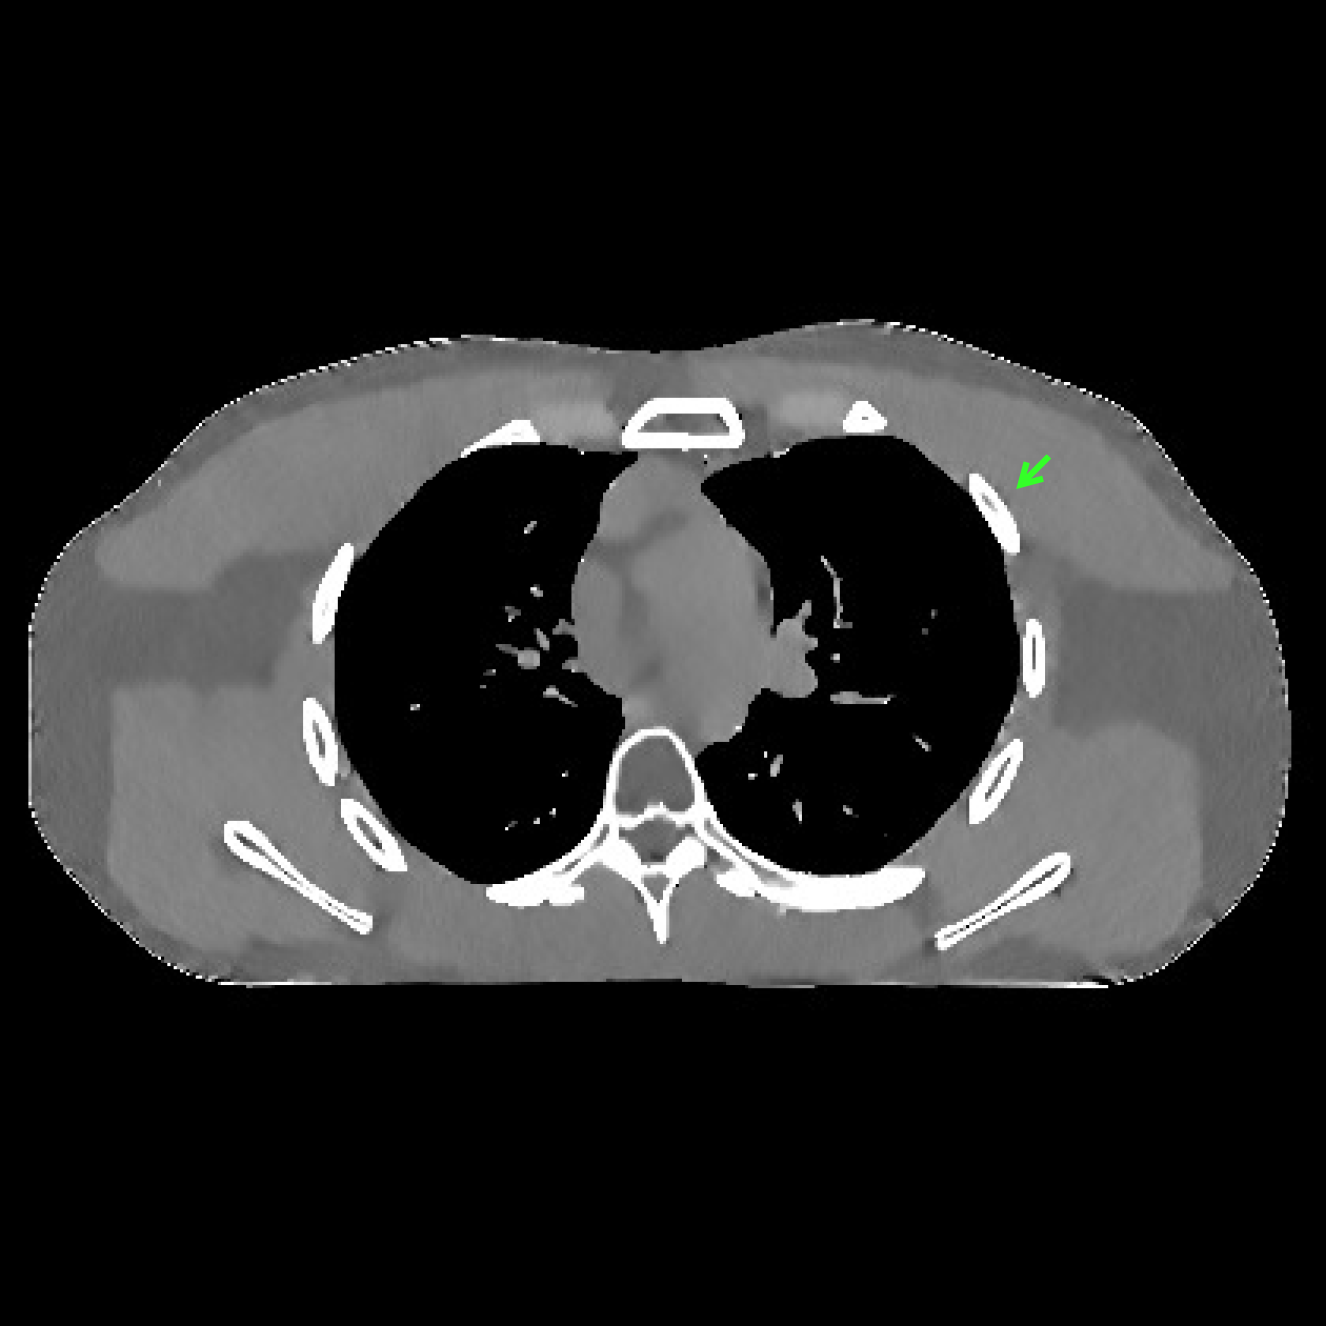

Fig.Β 7 shows the reconstructions (shown for the central axial plane in the 3D volume) for FDK (provided by GE Healthcare), PWLS-EP (corresponds to Fig.Β 8(a)), and PWLS-ULTRA with (corresponds to Fig.Β 9(a)). The PWLS-ULTRA reconstruction has lower artifacts and noise. Moreover, the image features and edges are better reconstructed by PWLS-ULTRA than by PWLS-EP or FDK.

Fig.Β 8 shows the reconstructions (shown for the central axial, sagittal, and coronal planes in the 3D volume) for PWLS-EP with different regularization strengths , denoted as a multiplicative factor of the parameter value in Fig.Β 7. Fig.Β 9 shows the reconstructions for PWLS-ULTRA (with patch-based weights) with different parameter combinations. For the sagittal and coronal planes, we show the central out of axial slices. Larger regularization strengths would achieve more noise reduction but simultaneously lower spatial resolution in PWLS-EP and PWLS-ULTRA, e.g., compare Fig.Β 8 and Figs.Β 9(a) and (d). Larger values of would achieve lower sparsities and more noise reduction but potentially oversmooth the image, e.g., compare Figs.Β 9(c) and (d). Small values of may introduce additional spurious noise in the PWLS-ULTRA reconstruction (compare Figs.Β 9(a) and (b)). Fig.Β 11 shows profiles of chest reconstructions (plotted from the central axial slice) for the PWLS-EP and PWLS-ULTRA methods. The profile locations are shown in green lines in Fig.Β 7. Both PWLS-EP with regularization strength X and PWLS-ULTRA (with patch-based weights) in Fig.Β 9(a) have lower noise than the PWLS-EP with regularization strength X. Though the spatial resolution of PWLS-EP with regularization strength X is close to PWLS-ULTRA in the selected soft-tissue regions, PWLS-ULTRA reconstructs bone and spine areas with higher resolution, and preserves small features better (compare the zoomed-in areas in Fig.Β 8 and Fig.Β 9).